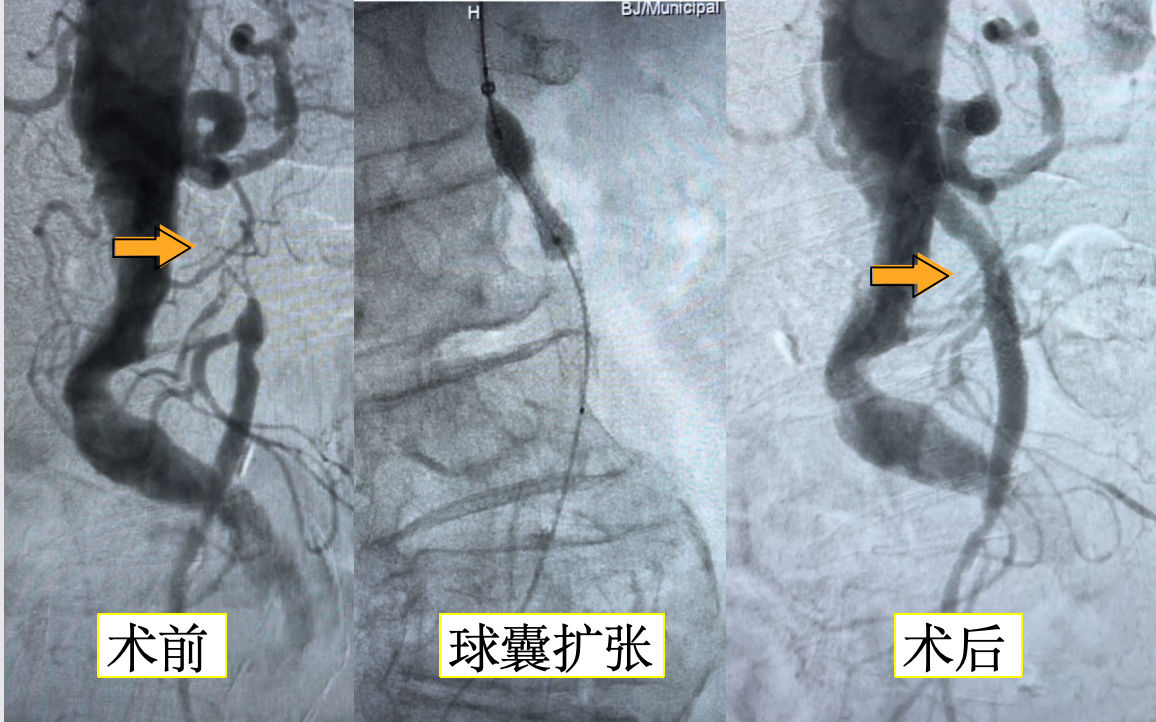

“这是缺血性肠病!”满新贺一下就发现了病人的主要病因。满大夫才把这一发现告诉了陈阿姨和她的家人,最终家人同意进行血管介入开通手术。在杨永久主任指导下,手术进行得很顺利,满医生和郑医生用球囊把狭窄的血管撑开,还放进了支架,让供应小肠的血液重新顺畅地流动起来。

术后第一天,奇迹就发生了——陈阿姨说她的腹痛明显减轻了,还主动要求吃饭呢!三天后,她就像换了个人似的,精神焕发地出院了。

腹部血管CTA、MRA及选择性血管造影对确诊SMA狭窄致肠缺血具有重要意义。血管腔内介入技术(球囊扩张及支架植入术)应用于SMA狭窄的治疗,是一种安全有效的方法。其疗效与手术治疗相当,且具有技术成功率高,并发症发生率低的优点,相对于外科治疗的高风险,对于高龄及有多种并发疾病的患者具有很大的优势。综上所述,肠系膜上动脉狭窄是一种需要引起重视的疾病,通过及时的筛查和有效的治疗,可以显著改善患者的生活质量。